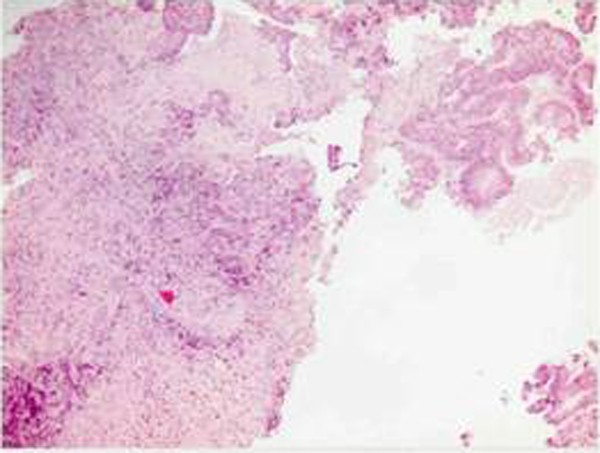

Other interesting element emerged evaluating the patient 60 years already described, belonging to group 2, wich were removed well seven liver metastases. The important aspect is determined by the mini-invasive surgical treatment of hepatic metastasis because the resection was performed with margins from 0.5 cm to 1 cm., under strict control intraoperative ultrasound and documented in various phases (Figure 4). The patient is alive today and has no metastatic relapse in routine follow-up.

Liver metastasis and colorectal carcinoma (synchronous surgery resection) (Group1)

We illustrate the case of a patient of 67 years operated in our hospital in 2005, belonging to group1, submitted to surgical treatment of simultaneous resection of adenocarcinoma of the ascending colon and liver metastasis. The patient is currently undergoing periodic monitoring (Figure 5). Finally we examine the case of another patient 71 years of age treated by us in 2007, which is also subjected to surgical treatment of synchronous resection of adenocarcinoma of the left colon and liver metastastasi two large 6x4 and 7x5 cm. (Group1) (Figure 6).